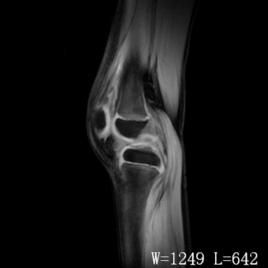

檢查

在髕韌帶與側副韌帶之間,沿關節間隙,有固定而局限的壓痛。麥氏征陽性。研磨試驗陽性。X線檢查有助於排除骨性病變或其它疾患。膝關節鏡檢查的確診率超過90%。